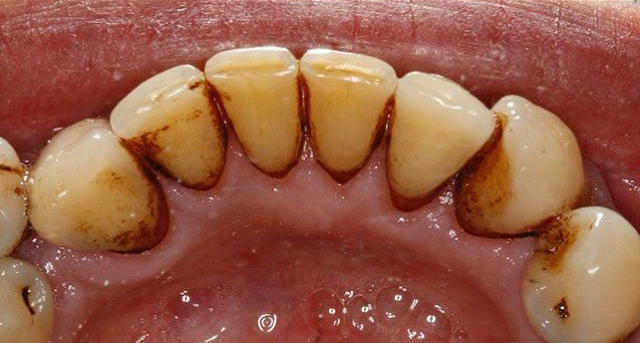

- Remove staining and discolouration caused by smoking or by drinking drinks such as red wine, tea and coffee etc

- Thoroughly remove dental plaque

Before and After Photos